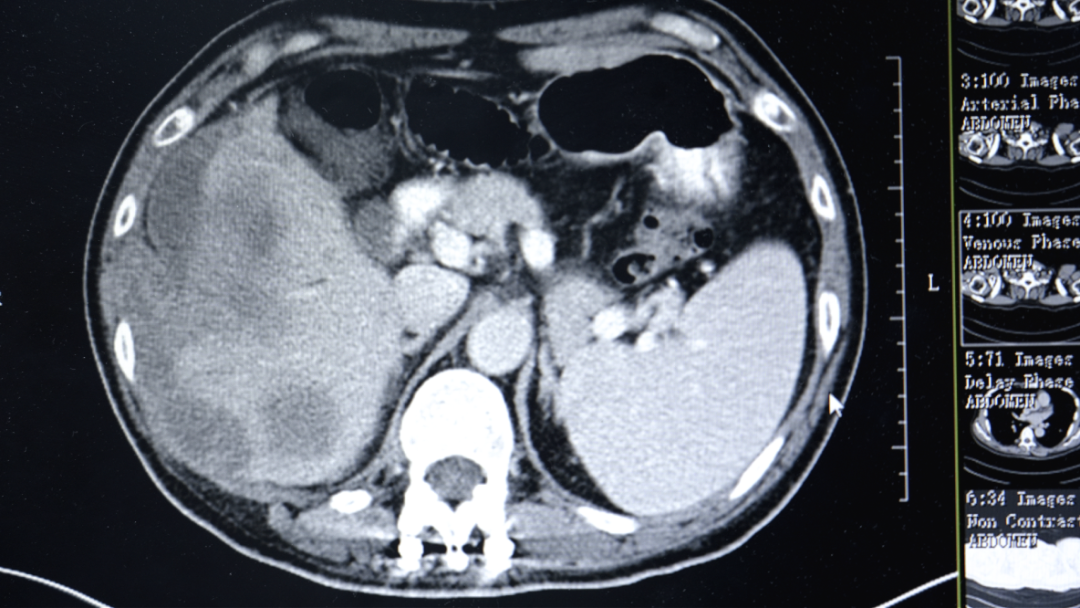

入院相关检查显示,勇哥的甲胎蛋白指标高达12.8万ng/ml(正常值<7ng/ml),肝功能评估为Child-Pugh B级(肝功能处于中度损害)。医疗六科李红梅主任团队根据他的具体情况,结合原发性肝癌CSCO指南,制定了靶向联合免疫的个性化治疗方案。

“吃了药,打了针,不怎么疼了,能吃饭能睡觉了。”几个疗程后,勇哥的生活质量明显改善。复查结果显示肿瘤得到控制,甲胎蛋白降至1.8万ng/ml。考虑到肝脏上病灶负荷太大,且紧靠周边,出血风险比较高,李红梅主任还是建议他进行肝动脉灌注化疗术(HAIC)。